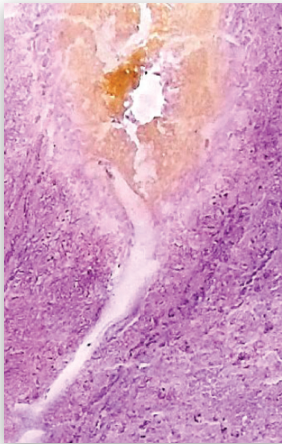

Режим “UltraPulse” - более безопасный по сравнению со стандартным импульсом при одинаковом уровне мощности: меньшее проникновение в ткани, менее травматичное рассечение в случае попадания импульса на мягкие ткани.

Перкутанная нефролитотрипсия.

Волокно 550 нм. Плотность = 1640 HU. Параметры: 3 Дж x 13 Гц = 39 Вт

Педаль нажата постоянно. Зеленый сигнал демонстрирует наличие излучения. Красный сигнал - его отсутствие.